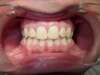

Classe 2

APRÈS